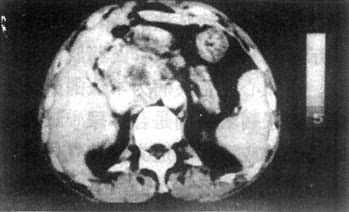

3.胰腺癌 CT表现为胰腺局部增大,呈肿块状隆起或呈分叶状增大。肿瘤的密度常与胰腺的密度相等,但其中常有坏死或液化而形成低密度区。增强扫描肿瘤常不增强或略增强,而正常胰实质增强明显,从而使肿瘤得以识别。这种密度的改变比看到肿块何能更重要。胰头癌侵犯、压迫胆总管引起梗阻性黄疸时,CT显示胆总管以上肝内外胆管扩张而胰头处胆总管突然狭窄、中断或变形。因此在梗阻性黄疸患者,必须沿扩大的胆管向下查寻,找到狭窄中断的位置。胰头部癌发生于钩突或累及钩突,若扫描层面不够低可能遗漏病变。胰头癌常阻塞胰管近段而使胰管扩大,表现为胰体中部偏前的管状低密度带,这也是胰头癌的一个重征象。胰腺癌进展,可使胰周脂肪层消失,邻近血管可被推移甚至包埋。肝门和腹膜后可出现淋巴结增大(图4-3-18)。

图4-3-18 胰腺癌CT表现 胰腺癌在MRI上可见胰腺局限性增大,该处轮廓不规则。T1WI上肿瘤信号稍低于正常胰腺和肝,其中坏死区信号更低;T2WI上肿瘤信号稍高且不均,坏死区则显示信号更高。一些间接征象如肝内外胆管扩张和胰管扩张是诊断胰头癌的重要依据,他们在T1WI上显示为低信号,T2WI上显示为高信号影像。 (责任编辑:泉水) |